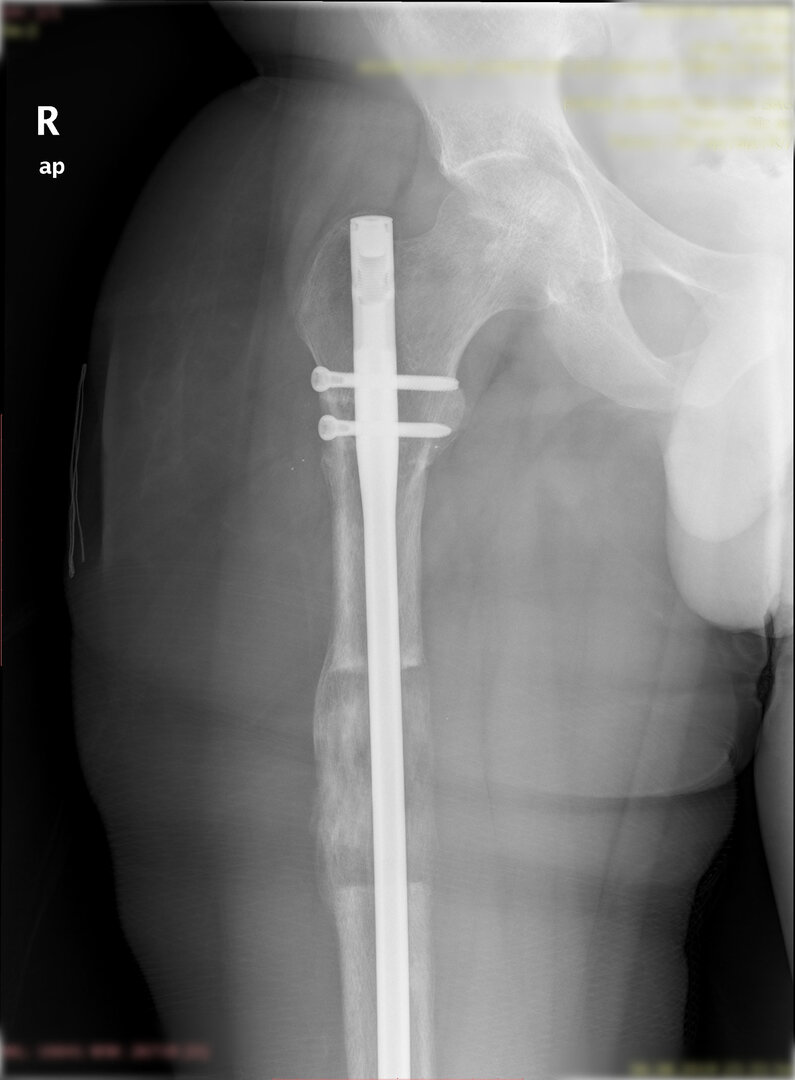

1. Manyetik intramedüller çivi ile uzatma:

Bu yöntemde uzatılacak kemiğin içerisine osteotomi sonrası bir manyetik intramedülller çivi yerleştirilir. Bu yöntemde dışarıdan yardımcı ek bir sistem yoktur. Uzatma hastanın bacağının üzerine dışarıdan konulan özel bir  mıknatıs ile sağlanır. Uzama istenilen miktara ulaştığında çivi yine kilitlenir ve kemiğin sertleşmesi beklenir. İki tür manyetik çivi bulunmaktadır: birincisi ilk jenerasyon olup içindeki dişli sistemine zarar vermemek adına hastanın yük vermesine izin verilmez; diğeri yani ikinci jenerasyon olan çivi ile hastanın yürümesine ve yük vermesine izin verilir.

Görüntüleri büyütmek için üzerine tıklayınız.

Görseli büyütmek için üzerine tıklayınız. Görseli büyütmek için üzerine tıklayınız. Radyografi görseli büyütmek için üzerine tıklayınız. Radyografi görseli büyütmek için üzerine tıklayınız. Radyografi görseli büyütmek için üzerine tıklayınız.